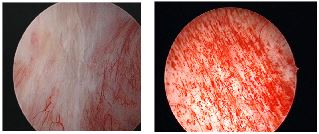

People with IC may have a bladder wall that is inflamed and irritated. In severe cases, the bladder wall inflammation can scar and stiffen the bladder so it cannot easily expand as it fills. Some women develop pinpoint bleeding of the bladder wall when stretched or have ulcers of the bladder lining which may lead to pain, urinary frequency, and urgency.

- Cystoscopy: A special telescoping camera to look inside the bladder and identify inflammation, pinpoint bleeding, or ulcers